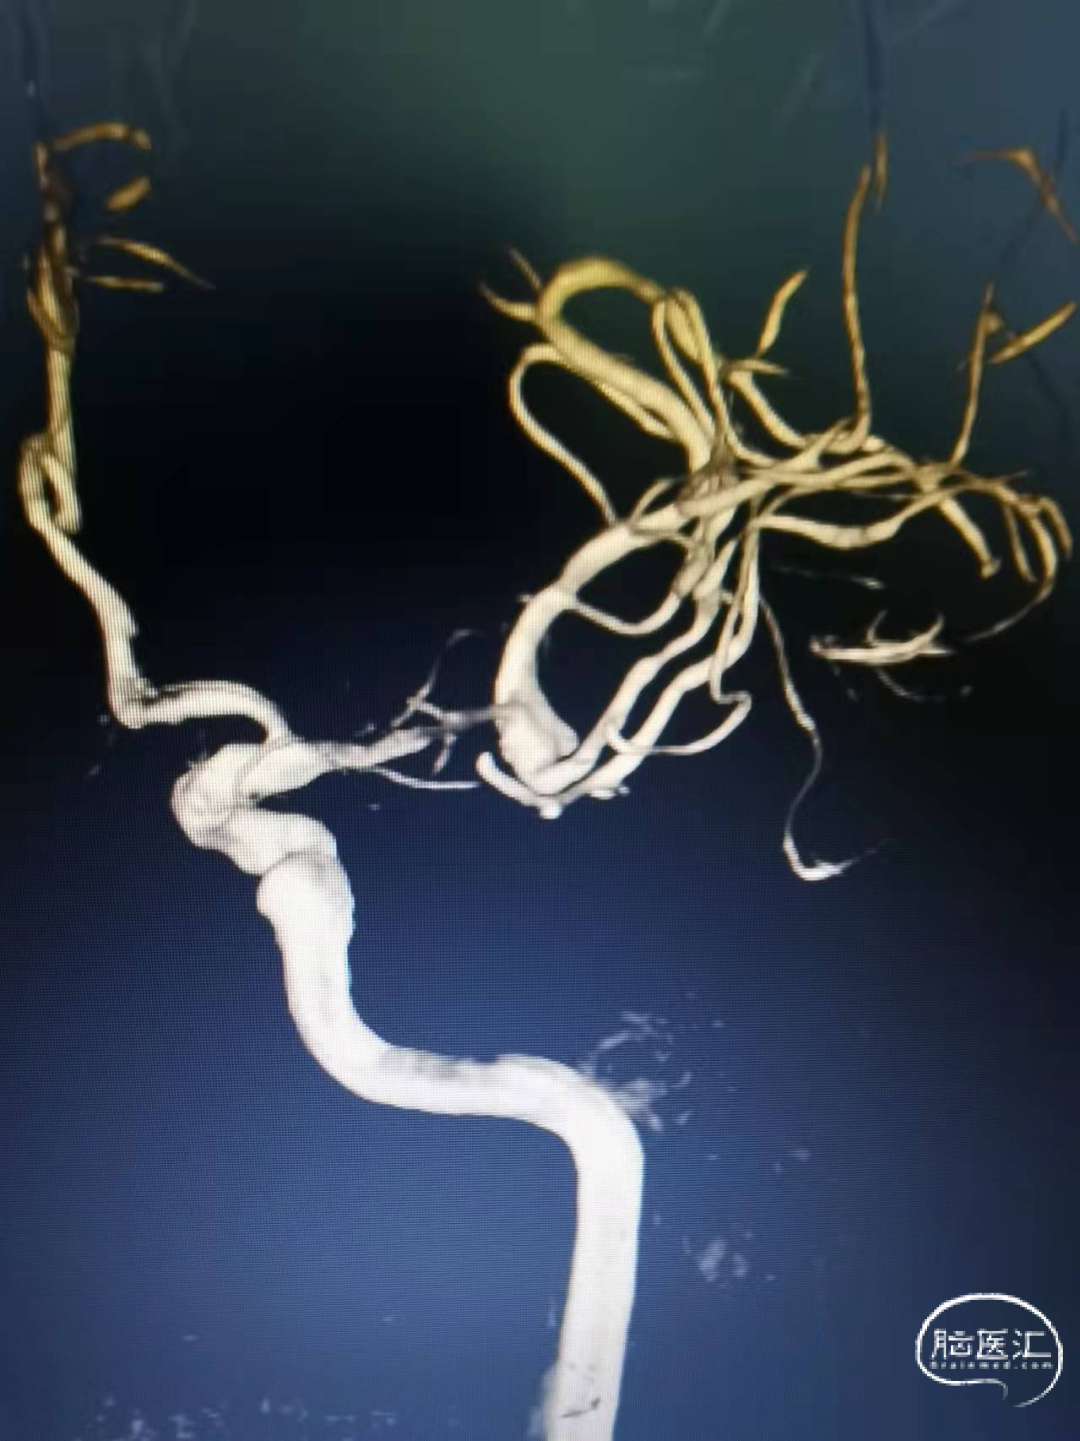

头颅MRA:右侧大脑中动脉分叉部结节状突起。

DSA:右侧大脑中动脉分叉部动脉瘤,约3*5mm,颈宽约5mm,伴上下干起始部扩张。

大脑中动脉近端M1直径2.82mm,远端1.83mm,上干1.85mm,下干1.7mm。

治疗思路:右侧分叉部动脉瘤,使用Atlas支架“Y”型辅助栓塞动脉瘤。